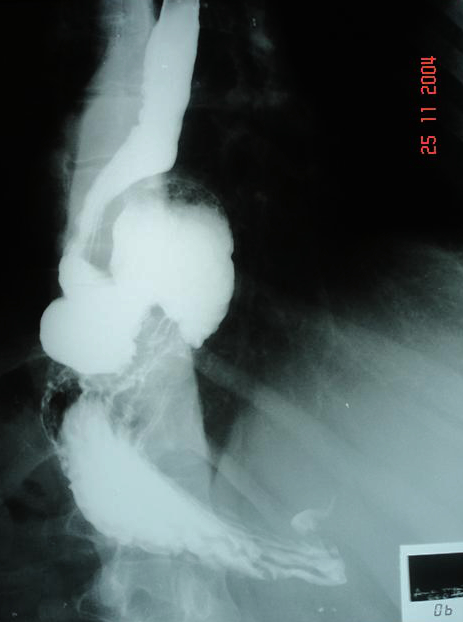

Radiografia mostrando o estômago dentro do tórax (hérnia de hiato grande)